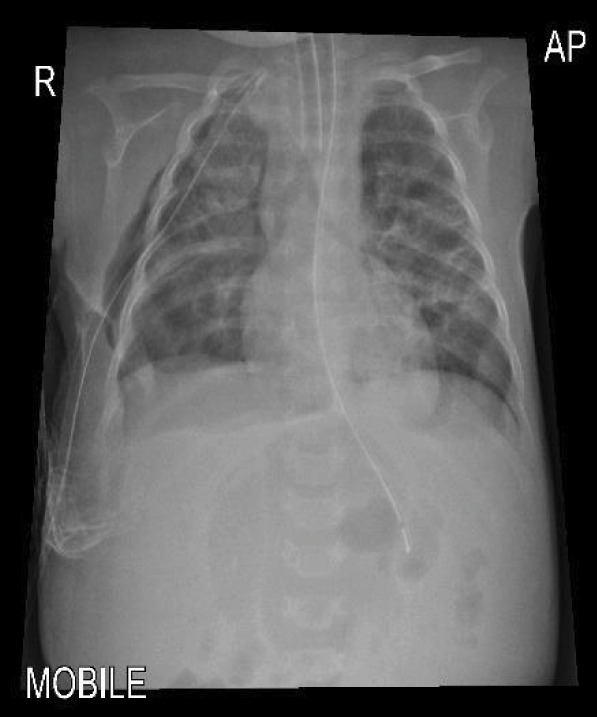

膈肌麻痹(DP)可由中枢神经系统病理或周围神经损伤引起。肋间胸引流术治疗气胸后直接损伤膈神经是一种少见的并发症。我们报告了一名4个月大的婴儿,早产27周,于2023年入住阿曼马斯喀特一家三级医院儿科重症监护室,患有严重呼吸道合胞病毒细支气管炎,需要插管和机械通气(MV)。他的病情因右侧气胸而复杂化,需要植入ICD。拔管后,患者持续呼吸急促,无法脱离无创通气。胸部x线及透视显示右侧膈球高且运动矛盾。他在右膈肌伸展术后明显好转,并于伸展术后第9天出院回家。

Diaphragmatic paralysis (DP) can occur due to central nervous system pathology or peripheral nerve injury. Direct injury to the phrenic nerve after intercostal chest drain (ICD) insertion for treatment of pneumothorax is an infrequent complication. We present a 4-month-old infant, ex-preterm 27 weeks, who was admitted to a tertiary care hospital paediatric intensive care unit in Muscat, Oman, in 2023 with severe respiratory syncytial virus bronchiolitis and required intubation and mechanical ventilation (MV). His illness was complicated by right-side pneumothorax that required ICD insertion. Post-extubation, he had persistent tachypnoea with the inability to be weaned from non-invasive ventilation. Chest X-ray (CXR) and fluoroscopy showed a high right diaphragm dome with paradoxical movements. He improved dramatically after the plication of the right diaphragm and was discharged home on the 9th day after the plication.